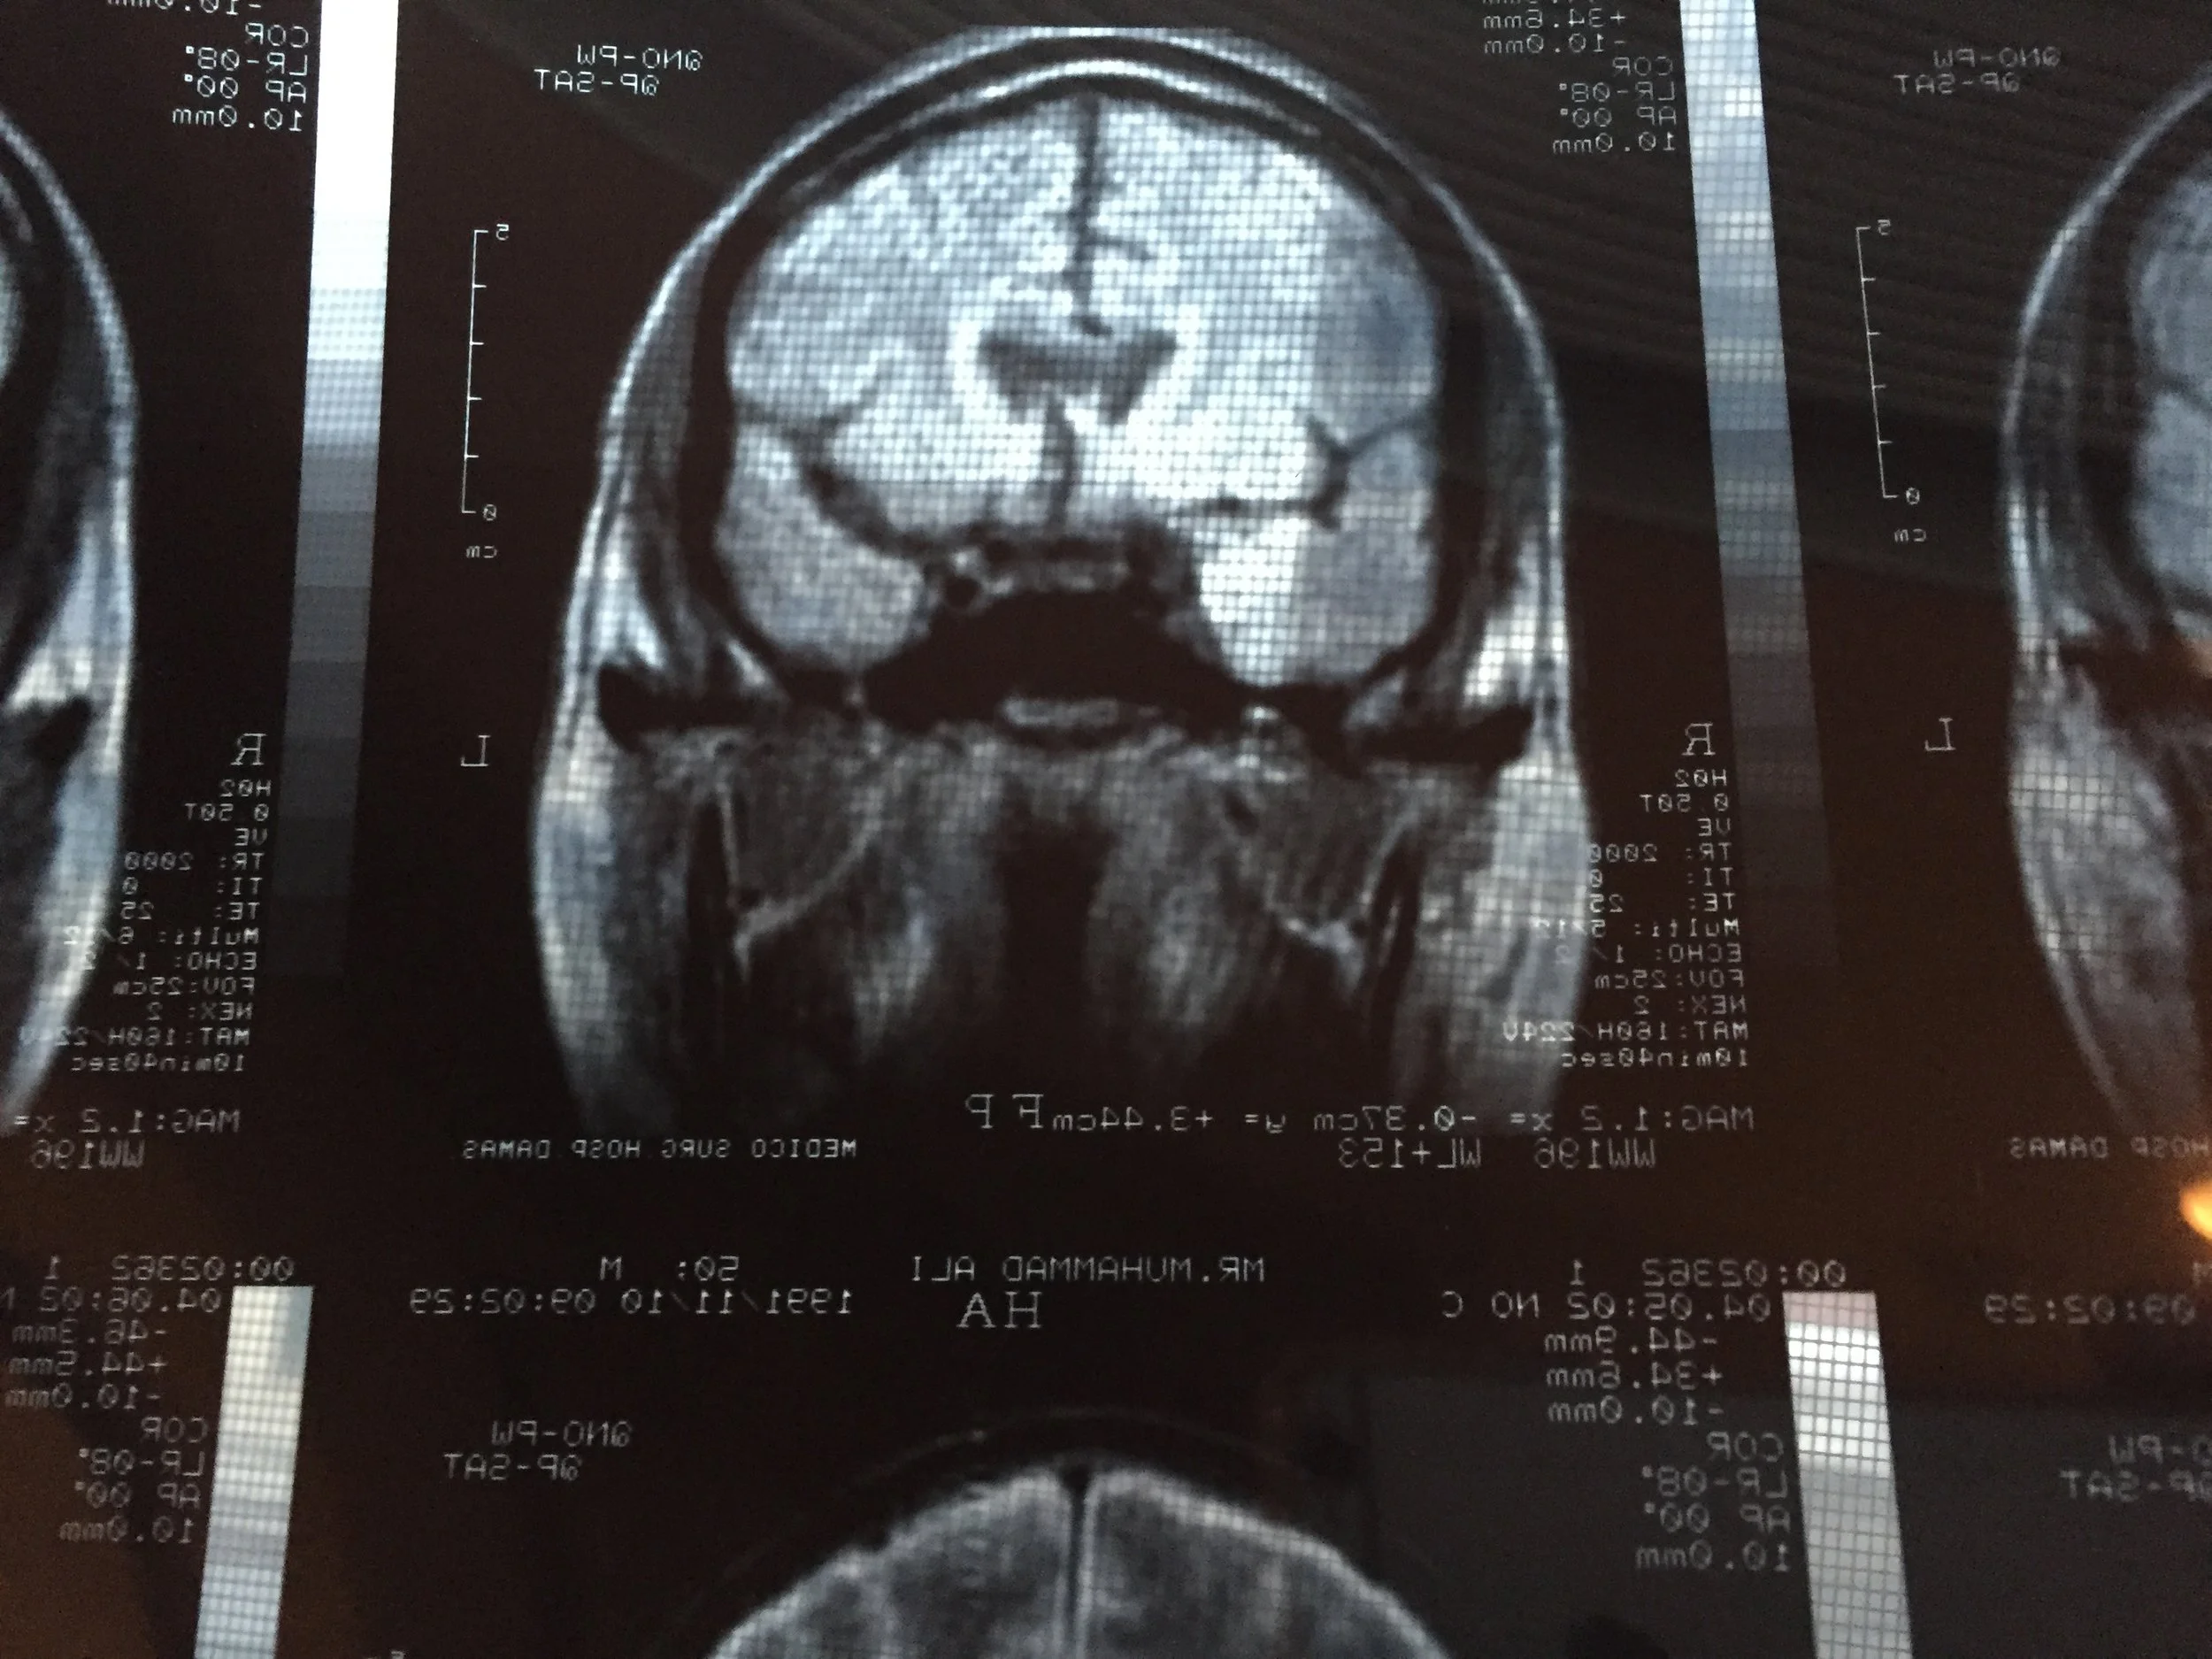

Muhammad Ali’s brain scans show troubling signs to modern neurologists. But is there any way to look back and trace the damage itself? Author Jonathan Eig looks for answers and uncovers shocking statistics. The fatal effects of Ali’s commitment to his sport are told in this week’s episode.